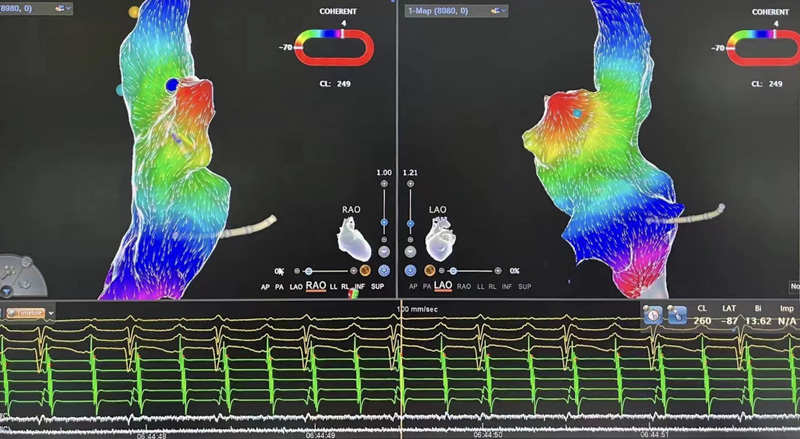

▲術(shù)中測標(biāo)

介入室內(nèi),心血管內(nèi)科電生理團(tuán)隊(duì)開始為患者進(jìn)行心電生理檢查,在三維系統(tǒng)指引下行激動(dòng)標(biāo)測提示心律失常起源于右心耳根部。右心耳是右心房的盲端,非常菲薄,大約只有1-2mm,附近有竇房結(jié)、上腔靜脈等重要結(jié)構(gòu),在此處消融,有心臟穿孔、損傷竇房結(jié)導(dǎo)致心臟停搏等風(fēng)險(xiǎn)。